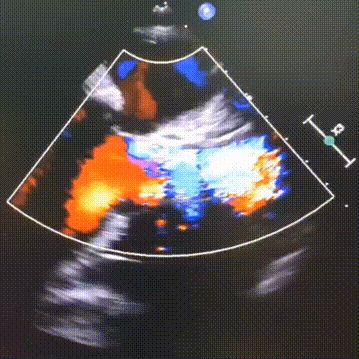

超声看位置合适,无反流

超声看左冠窦侧6mm左右

完全释放,无反流

超声看完全释放下滑至7mm

几乎无反流

几乎无瓣周漏